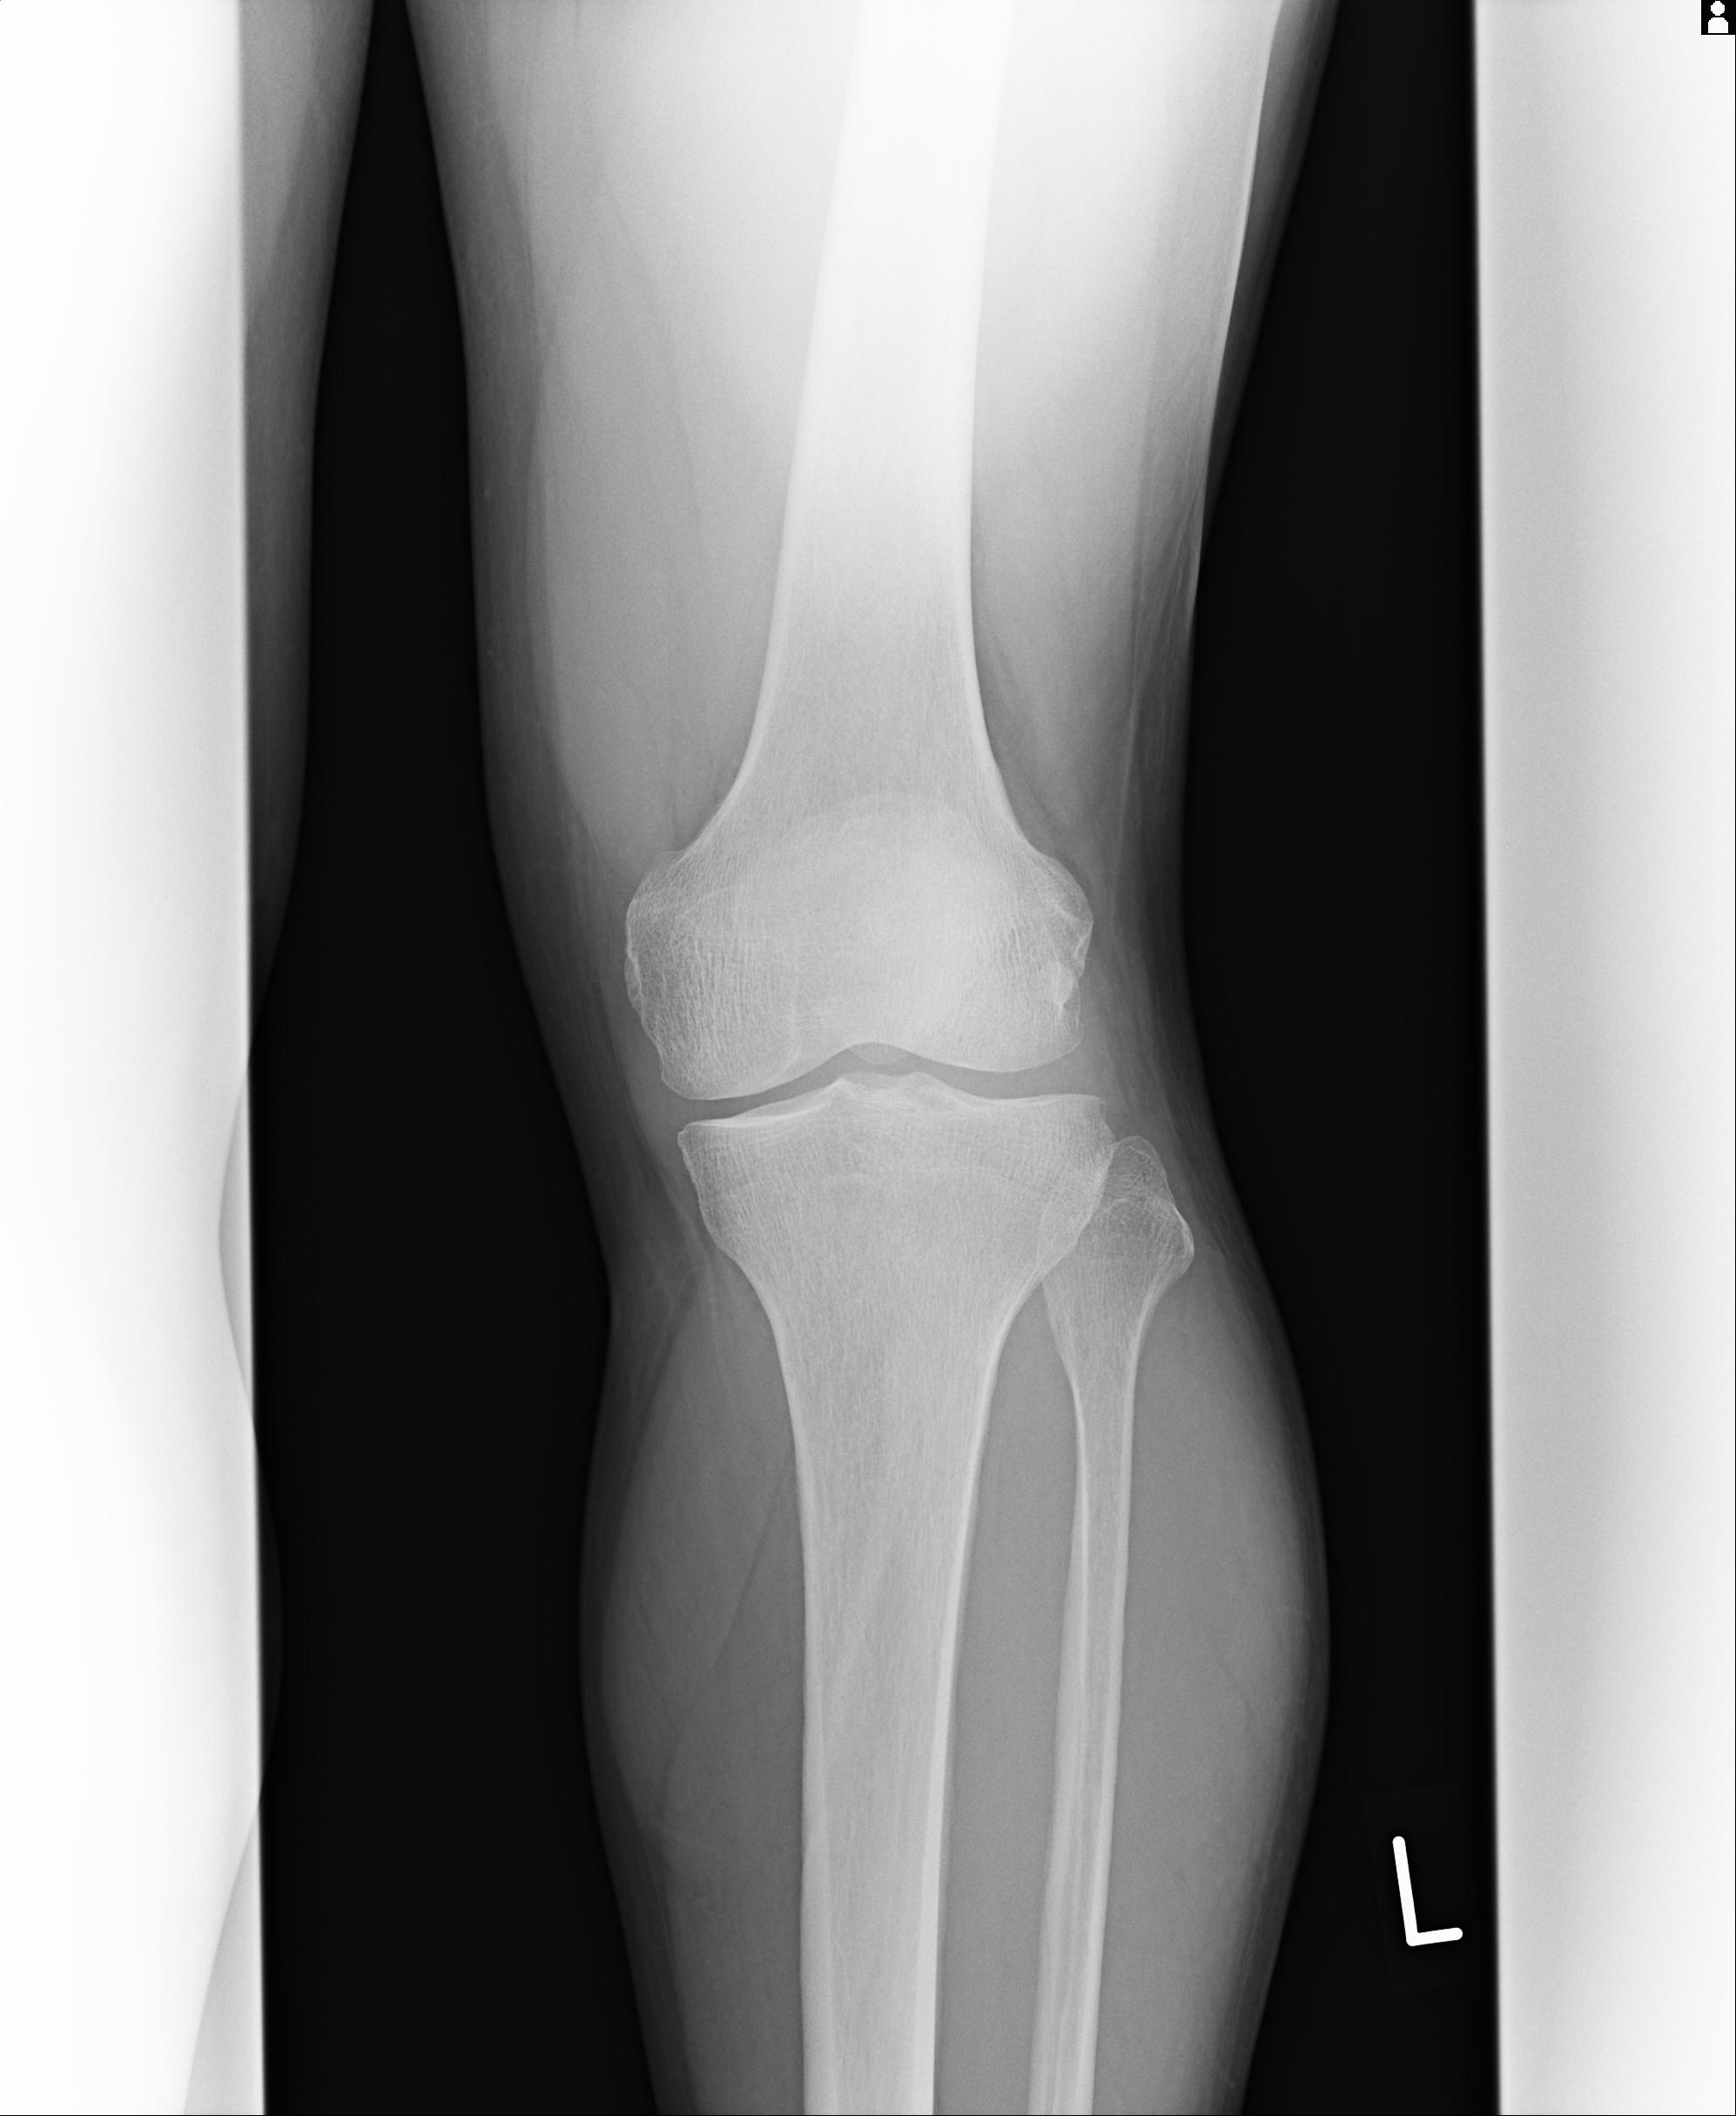

91983 11/16 左膝 2R 11/18 2R 55歳男性 脛骨骨切り術